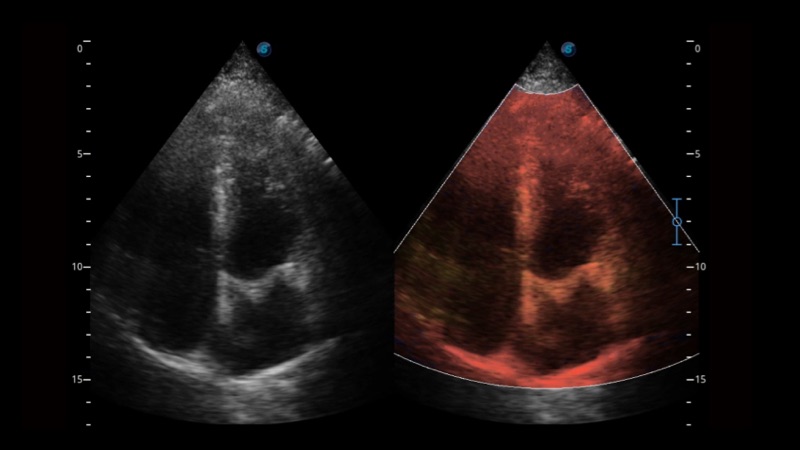

组织多普勒

组织多普勒成像功能,可提供心肌运动速度和其他临床信息,使临床医生能够分析和比较患者心脏不同部位的运动。